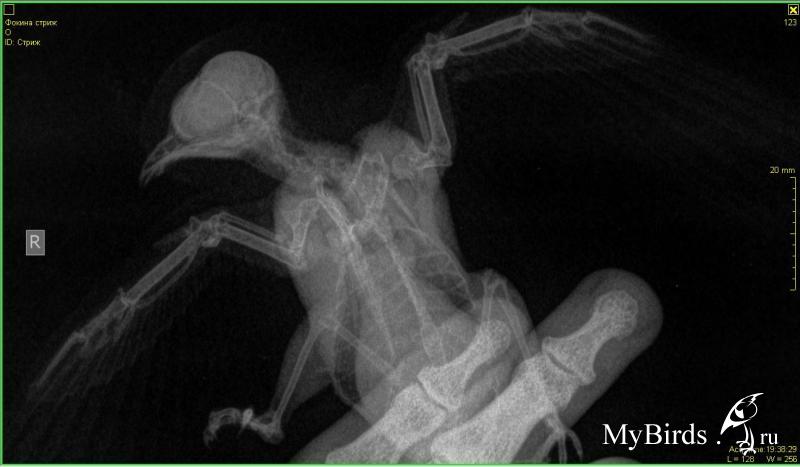

lilamor Опубликовано 25 июля, 2017 #1 Опубликовано 25 июля, 2017 Здравствуйте! Хочу спросить про этого стрижа. Он живет у моей знакомой. Привезли с переломом. Первый снимок (две фотографии) 30 мая, второй (тоже две) - 29 июня. Из лекарств она давала B1 и мелоксикам. Говорит, не может набрать высоту. Кормит сверчками и тараканами, чистит их как положено и тренирует его. "По распорядку - кормлю утром в 8:00 (примерно, бывает на выходных позже), вечером в 18:00ночью в 00:00 Тренировки - каждый день по буднях 1 раз вечером пускаю на накрытое покрывало, на выходных раза 3 в день.Перестал крылохлопить, когда сообразил, что внизу пол, а для него пол - это свобода))или висит на покрывале и не шелохнется. Если беру в ладошку- он слетает на покрывало, это единственный вариант тренировки для него, по-другому не получается. я его просто беру над ковром и над покрытым покрывалом слева (то есть покрывало закреплено на чем-то высоком у стены, спинки дивана, а к другой стороне оно опущено под углом). и держу - он начинает активничать и летит вниз на мягкое. Беру его всегда в перчатках! Хотя сначала не делала этого, о чем жалею( запылились немного перья, я периодически хлоргексидином прохожусь ватным диском."Вот тут видео как он летает https://vk.com/im?sel=26594438&z=video2...6a542ae99c5e316. Вопрос по снимкам: лучше или хуже стало? Что еще можно сделать? Есть надежда на полёт? Или он навсегда останется домашним питомцем?

Anysya Опубликовано 25 июля, 2017 #2 Опубликовано 25 июля, 2017 небольшая надежда у птицы была. так как смещение незначительное, хотя и перелом в очень плохом месте. т.е. результат был бы гадательным.шанс на успех был при условие полного покоя на полтора месяца. никакого обезбаливания - только боль заставляет сидеть спокойно первые две недели и кость встает на место, срастается идеально. мелоксикам в таком случае снижает шанс на подобный исход практически на 100%. а заставлять птицу тренироваться и летать с уже нарушенным сращиванием и недостаточной костной мозолью - именно для этого следующий месяц после первых двух недель - это просто издевательство. тем более, стриж и не нуждается в подобных тренировках и сам способен решить когда и как ему тренироваться.в общем, шансов на вылет практически не осталось. птицу жаль.